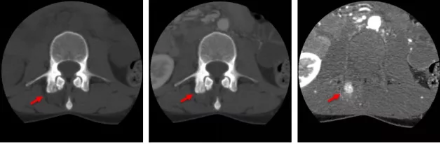

骨智能柔性減影成像功能發(fā)現(xiàn)隱匿骨占位病灶

相比傳統(tǒng)成像方式,肺部柔性減影技術(shù)通過人工智能,對平掃數(shù)據(jù)和CT肺動脈血管掃描數(shù)據(jù)進行智能比對,解碼并識別各個器官(肺、氣管、肺動脈、肺靜脈、主動脈等)的空間位置,并在三維空間中進行體素級的柔性配準,從而極大提升了不同序列數(shù)據(jù)的空間位置的一致性。通過肺部柔性減影技術(shù)可得到肺強化碘圖,可以顯示出傳統(tǒng)CTPA圖像看不到的小栓塞病變,提高了栓塞檢出率,其結(jié)果甚至可與SPECT吻合。